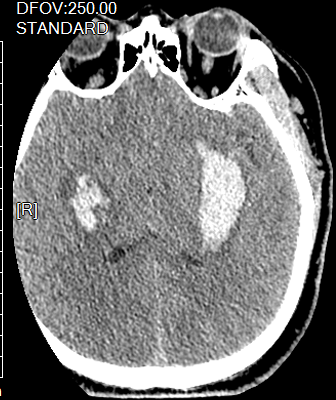

影像诊断头颅一 右基底节出血.

图片尺寸1920x1920